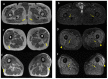

In the present study, through a case series, we highlighted the role of magnetic resonance (MR) in the identification and diagnosis of peripheral neuropathies. MR neurography allows the evaluation of the course of nerves through 2D and 3D STIR sequences with an isotropic voxel, whereas the relationship between nerves, vessels, osteo-ligamentous and muscular structures can be appraised with T1 sequences. Currently, DTI and tractography are mainly used for experimental purposes. MR neurography can be useful in detecting subtle nerve alterations, even before the onset of symptoms. However, despite being sensitive, MR neurography is not specific in detecting nerve injury and requires careful interpretation. For this reason, MR information should always be supported by instrumental clinical tests.